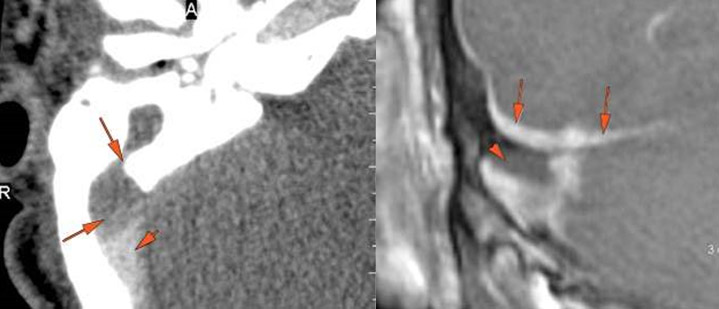

The external auditory canal shows abnormal soft tissue thickening. [Yes/No]

External auditory canal bone is eroded. [Yes/No]

The petrotympanic fissure is eroded. [Yes/No]

There is an erosive process, subperiosteal or otherwise spreading along the anterior-inferior aspect (extracranial aspect) of the petrous apex involving the bony Eustachian tube and/or carotid canal. [Yes/No]

The petrous apex is abnormal. [Yes/No]

The facial canal including the labyrinthine, tympanic and descending portions and nerve are abnormal. [Yes/No]